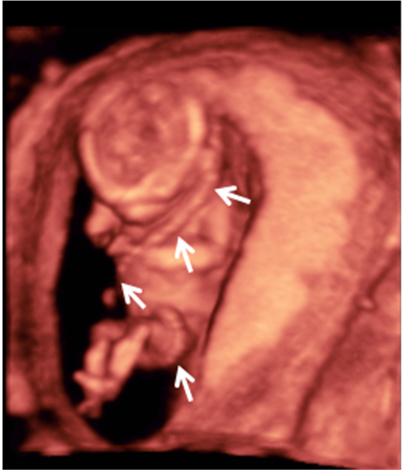

En la semana 12 de gestación, la embarazada aún no nota los movimientos del bebé que crece dentro de su útero. Pero en esta ecografía en 4D se observa sus vigorosos movimientos.

La curiosa ecografía de este feto de 12 semanas comienza con la imagen de espaldas. El niño se gira hasta colocarse de perfil y es entonces cuando empieza a mover brazos y piernas con agilidad. Todo un signo de bienestar fetal.